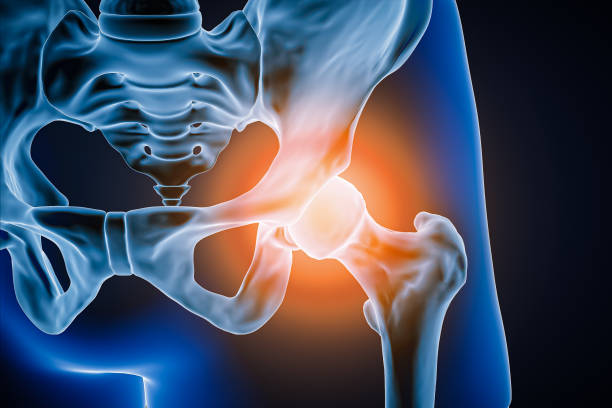

골반통증은 많은 사람들이 겪는 건강 문제 중 하나입니다. 장시간 앉아있거나 일을 많이 하다보면 골반 주변 근육이 약해지고 불균형해지는 경우가 많아 골반통증이 발생할 수 있습니다.

이런 골반통증의 경우 근육이 약해지거나 자세불량 등 다양한 이유가 있는데요.